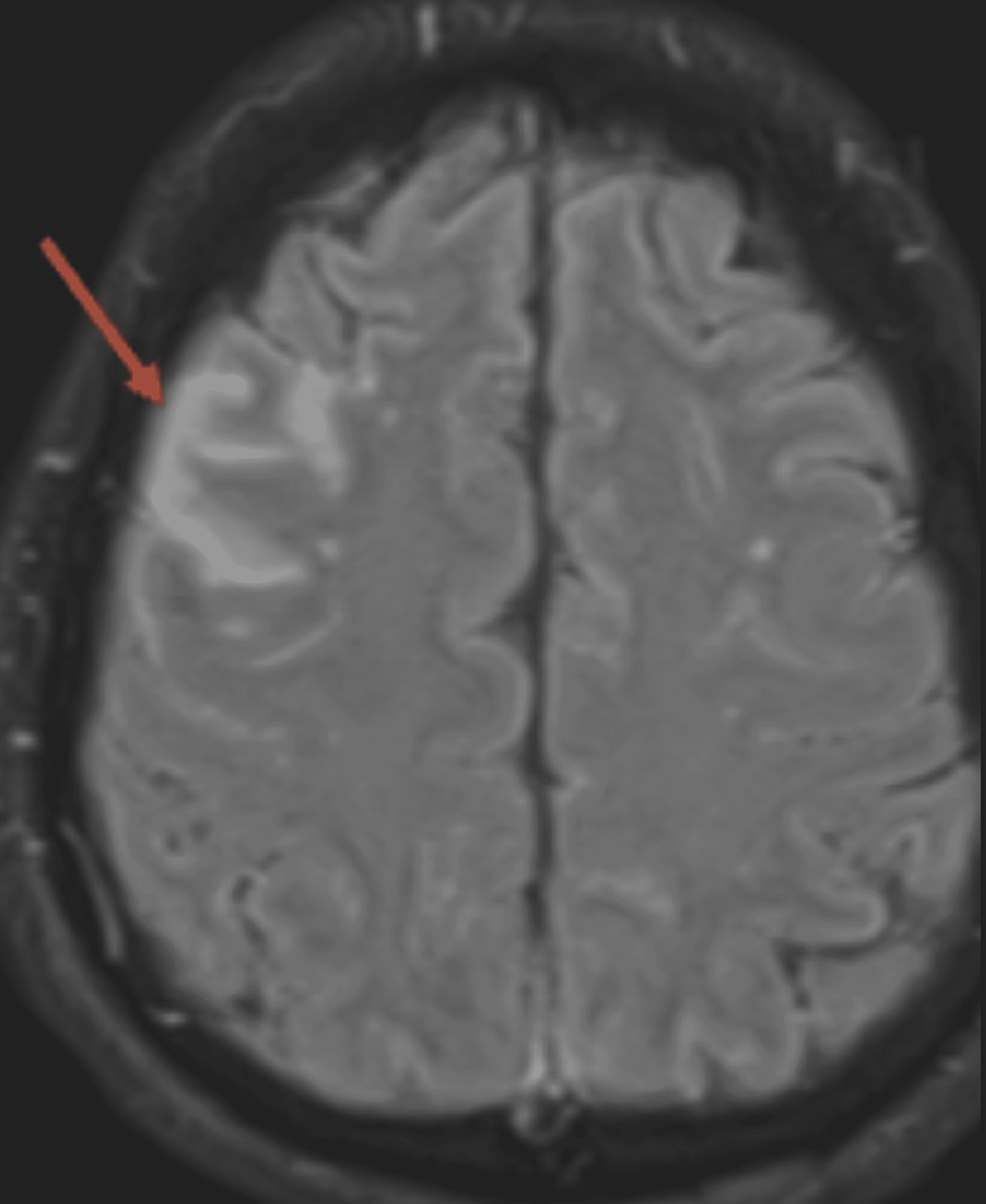

A Sharp Rise in Autoimmune Encephalitis in the COVID-19 Era: A Case Series

Background: Autoimmune encephalitis was very rare prior to the current pandemic. A sharp rise in cases has been observed from March to August of 2022 in Los Angeles. Such an...

Conclusions: This observation has important implications: (1) We may be entering an era of heightened autoimmune encephalitis. (2) These occurrences may be post-infectious in nature at this point of the pandemic. (3) Mostly GAD and VGKC antibodies have been identified (10 of them), which may point toward a new direction of research from a...